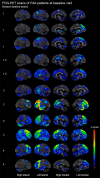

Agrammatic aphasia affects grammatical language production and can result from a neurodegenerative disease. Although it typically presents with concomitant apraxia of speech, this is not always the case. Little is known about the clinical course and imaging features of patients that present with agrammatism in the absence of apraxia of speech, which we will refer to as progressive agrammatic aphasia. We aimed to make a detailed description of the longitudinal clinical, linguistic, and neuroimaging features of a cohort of 11 patients with progressive agrammatic aphasia to provide a complete picture of this syndrome. All patients underwent detailed speech and language, neurological and neuropsychological assessments, 3 T structural and diffusion tensor imaging MRI, 18F-fluorodeoxyglucose and Pittsburgh compound B PET. The 11 patients were matched by age and gender to 22 patients who had mixed apraxia of speech and agrammatism. The progressive agrammatic aphasia patients performed abnormally on tests of language, general cognition, executive function, and functional ability at baseline and declined in these measures over time. Only two patients eventually developed apraxia of speech, while parkinsonism was absent-to-mild throughout all visits for all patients. When compared to the patients with mixed apraxia of speech and agrammatism, the patients with progressive agrammatic aphasia performed better on tests of motor speech and parkinsonism but more poorly, and declined faster over time, on tests of general aphasia severity, agrammatism, and naming. The patients with progressive agrammatic aphasia also showed different neuroimaging abnormalities, with greater atrophy, hypometabolism and white matter tract degeneration in the prefrontal and anterior temporal lobes compared to patients with mixed apraxia of speech and agrammatism. These differences were more pronounced as the disease progressed. These results demonstrate that progressive agrammatic aphasia has a different clinical disease course and different underlying neuroanatomical abnormalities than patients with the more common syndrome of mixed agrammatism and apraxia of speech. This supports the distinction of progressive agrammatic aphasia and has implications for the classification of patients with agrammatic aphasia.